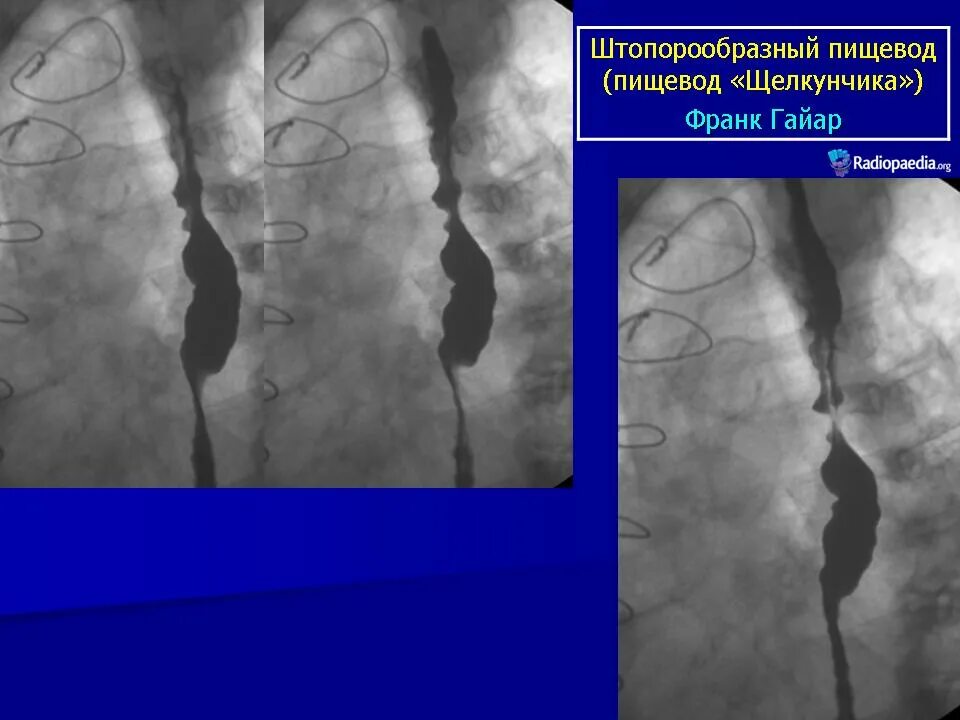

Кольцо шацкого в пищеводе что это